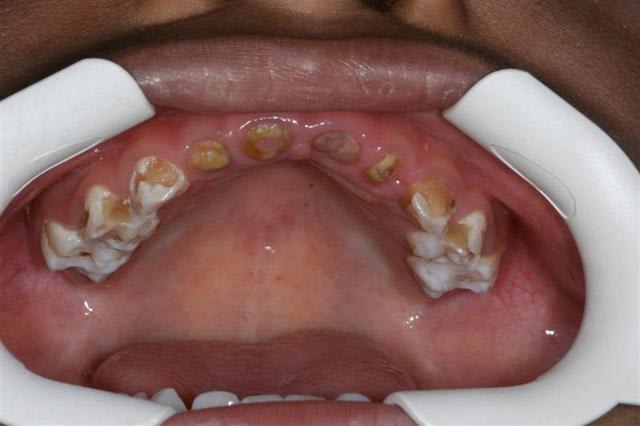

couronne pedo